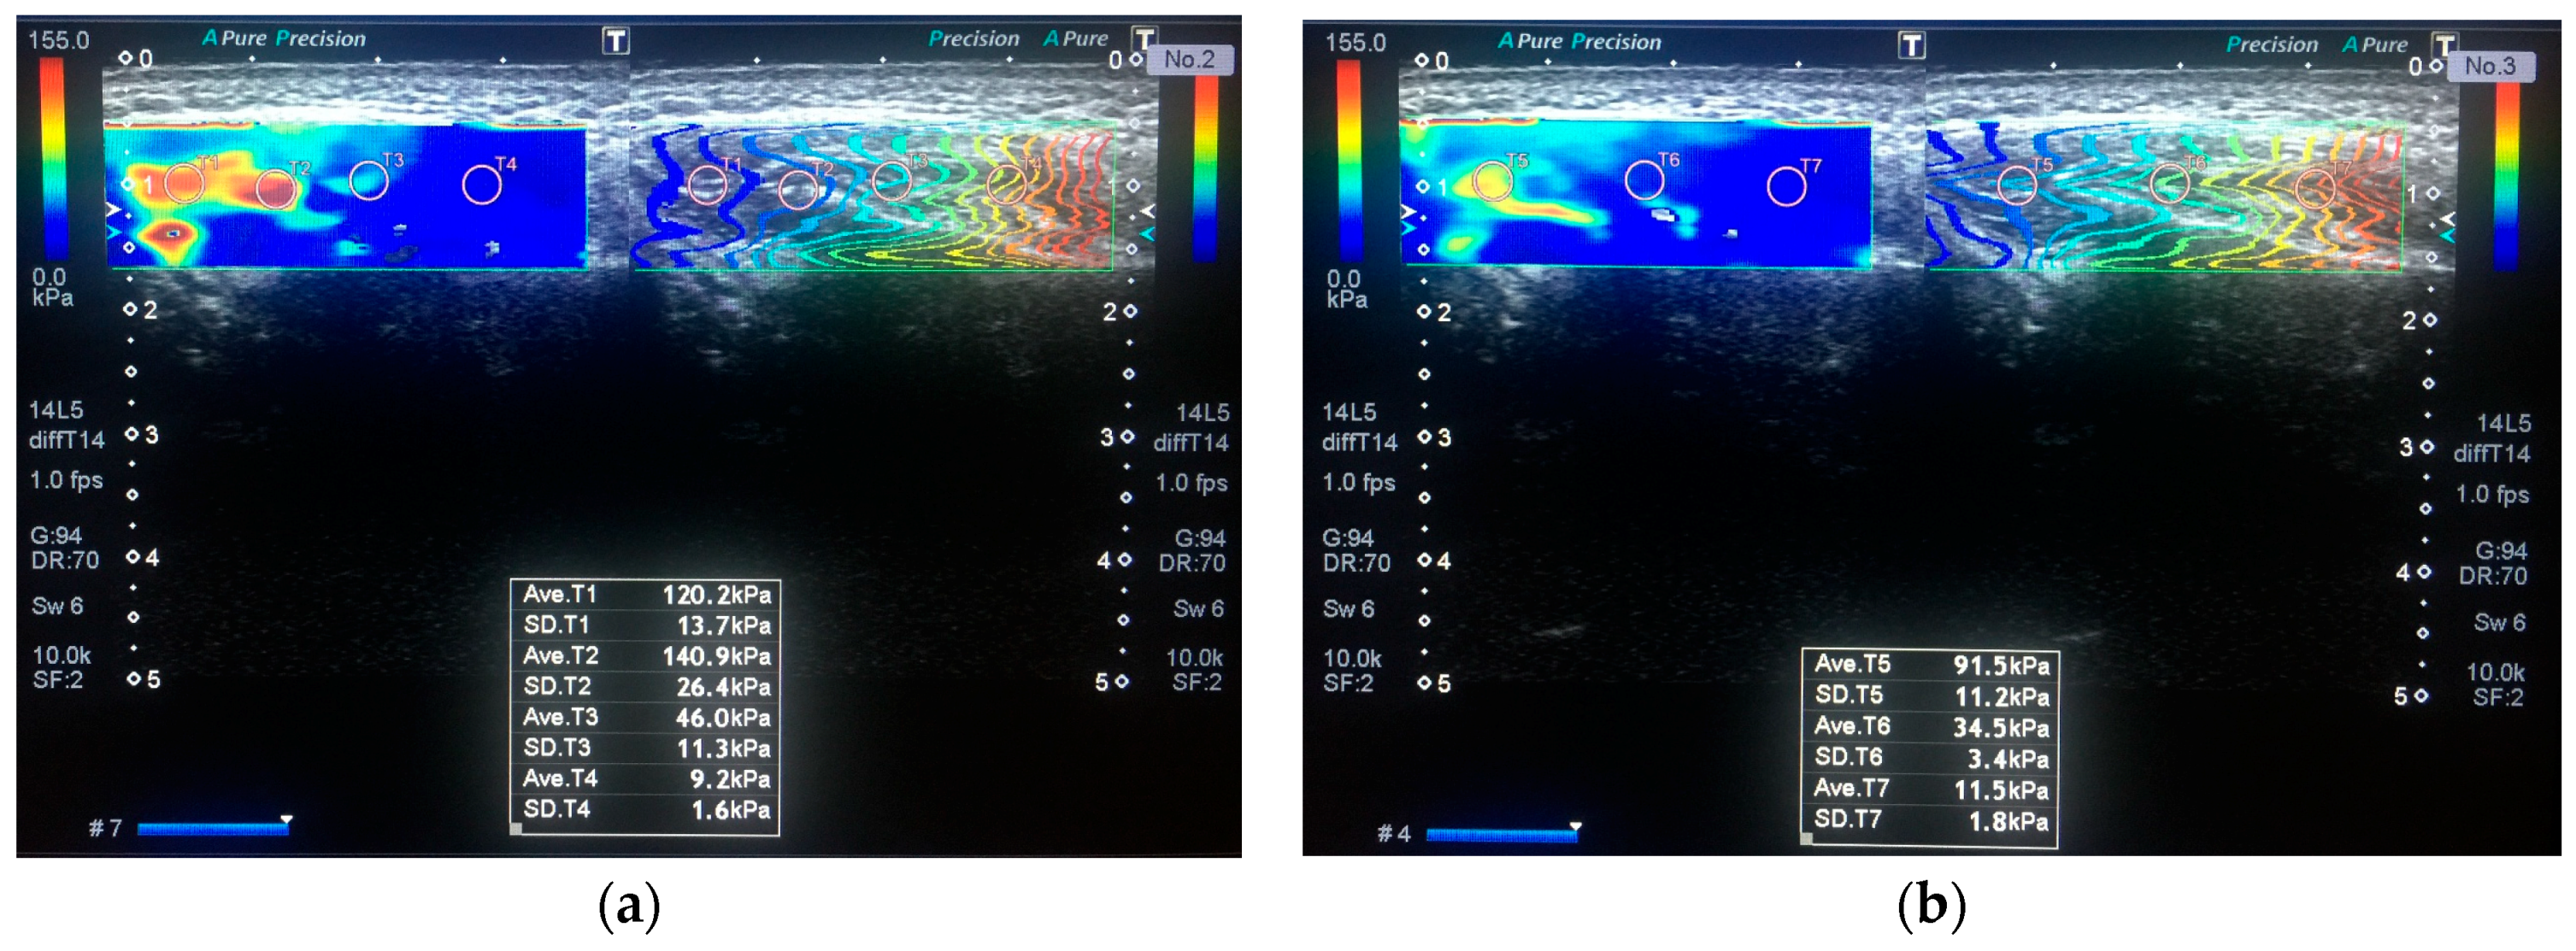

2.3. Imaging and Measurements